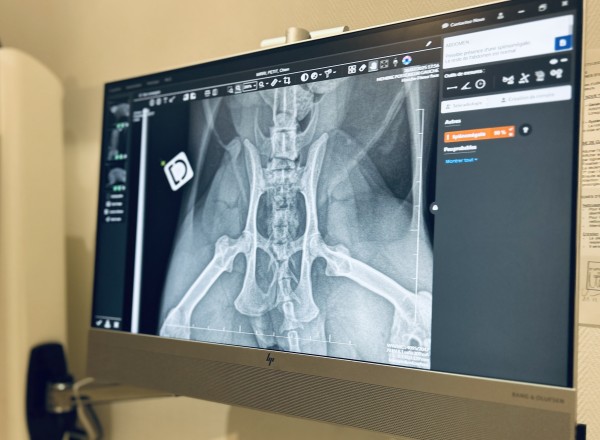

Des outils diagnostiques de grande précision et très récents au sein de la clinique

•  Radiographie numérique

La clinique dispose d'une radiographie numérique de dernière génération couplée à l'IA permettant d'obtenir des clichés de grande qualité.

Les clichés peuvent vous être envoyés en format numérique.